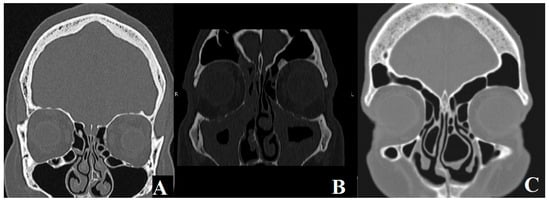

- CB is defined as the pneumatization of the middle turbinate. It can obstruct the air passage by blocking the middle nasal meatus or cause mucosal edema, inflammation, drying, and headaches by impeding the ethmoid infundibulum.

- PMT refers to an abnormal curvature of the middle turbinate, in which the convex surface faces laterally instead of medially. This abnormality can obstruct the drainage pathway of the middle meatus.